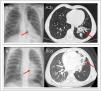

Case 1 Boy aged 8 years with an unremarkable history presenting with productive cough of one year’s duration and chronic left lower lobe (LLL) atelectasis observed in chest X-rays (Rx) and bronchiectasis with bronchial wall thickening and mucous content in the chest CT scan (Fig. 1). The patient underwent flexible bronchoscopy, with visualization of an intrabronchial foreign body (FB) in the LLL that was removed in the same procedure (Fig. 2; Appendix B video) and turned out to be a sunflower hull. (A) Case 1: (1) chest X-ray showing atelectasis of the left lower lobe (red arrow), (2) computed tomography showing bronchiectasis in the left lower lobe (red arrow). (B) Case 2: (1) chest X-ray showing infiltration of left paracardiac region (red arrow), (2) computed tomography showing atelectasis in the lingula and bronchiectasis (red arrow). Boy aged 2 years, previously healthy, who abruptly started coughing blood while jumping on a trampoline. The chest Rx revealed infiltration in the left paracardiac region and the chest CT scan a poorly defined mass in the left main bronchus with atelectasis of the lingula and bronchiectasis (Fig. 1). Flexible bronchoscopy allowed visualization of a FB and substantial edema and inflammation of the adjacent mucosa, which precluded its removal (Fig. 2). After administration of intravenous steroids and antibiotherapy, the FO, which was a piece of branch, was removed by rigid bronchoscopy.